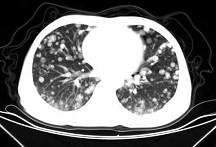

问题 男,42岁,肝区痛一月余,最近二周咯血丝痰,胸部CT如图,最可能的诊断为 ( )

选项 A、肺转移瘤 B、韦格肉芽肿 C、过敏性肺炎 D、结节病 E、葡萄球菌肺炎

答案 A